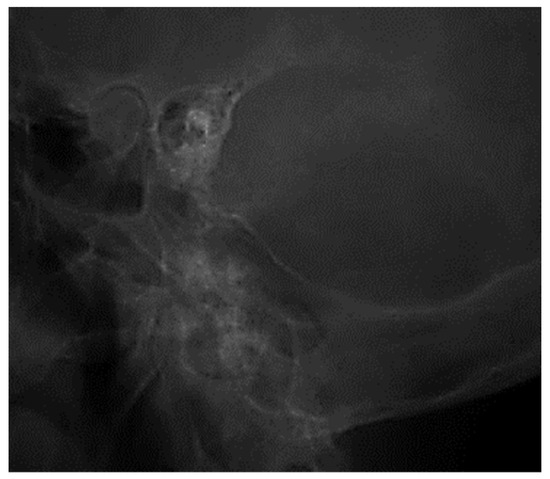

3.1.1. Conventional Radiology

3.1.2. Computed Tomography and Magnetic Resonance Imaging